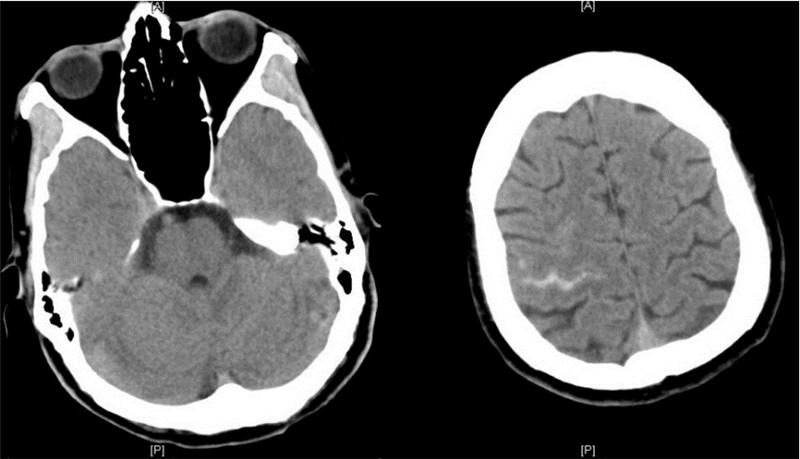

检查资料:颅脑CT示 左小脑、左额叶小片状低密度影,右中央沟少量蛛网膜下腔出血(图 2)。腰穿检查:脑脊液压力 80 mmH2O(1 cmH2O=0.098 kPa),外观无色透明,潘氏试验(+),细胞总数32.00/μL,白细胞0.00/μL,糖4.14 mmol/L,氯165.9 mmol/L,微量总蛋白90 mg/dL,抗酸染色(-),墨汁染色(-),细菌、真菌涂片(-),细菌、真菌培养(-)。PCT:5.78 ng/mL。

| 左小脑、左额叶小片状低密度影,右中央沟少量蛛网膜下腔出血 图 2 患者颅脑CT(2013-05-04) |

提示:局限性蛛网膜下腔出血;不排除急性脑梗死。

住院医师(3) 患者白细胞、中性粒细胞明显升高,PCT 5.78 ng/mL,支持细菌感染,但腰穿结果不支持颅内感染,故感染灶不明确。体温≥38.5 ℃时,可抽血培养,查明是否血行感染,并检查全身皮肤隐匿感染灶。颅脑CT示低密度灶,可能为急性脑梗死,但由于就诊时间很短,可间隔24~48 h复查CT以明确;少量局限性蛛网膜下腔出血与症状、体征不符,可能为伴发改变,需进一步行头颅MRI、MRA检查以明确。